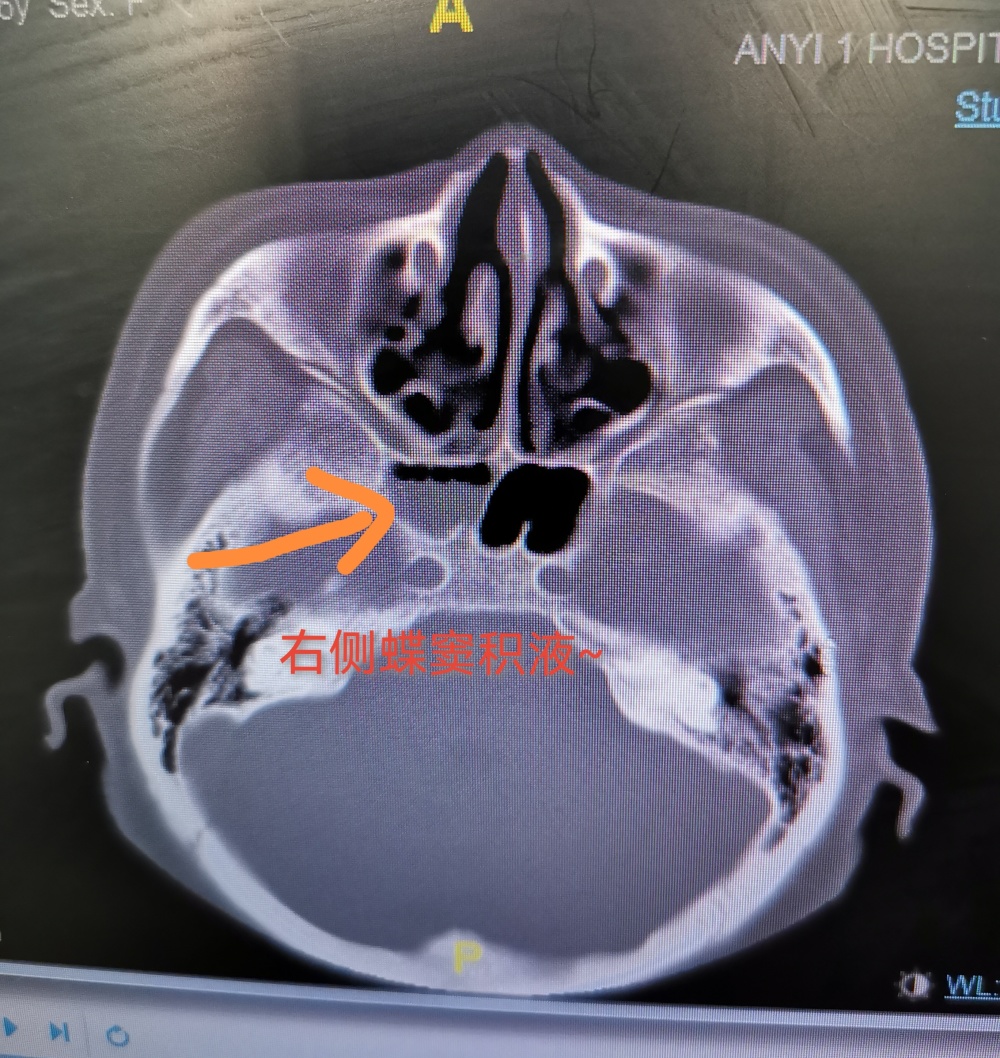

女子“鼻涕”流不停 一查竟是脑袋“漏”了

大皖新闻讯  近期,寿县的王大妈经常会流“清鼻涕”,以为是感冒,吃点感冒药就能慢慢痊愈了。没想到,这“鼻涕”竟是脑脊液。经过相关检查,发现王大妈的脑袋“漏”了。

十几天前,王大妈发现自己流鼻涕的现象增多,尤其是低头、咳嗽的时候,右侧鼻腔鼻涕“滴滴答答”流个不停,吃了感冒药后,仍不见好转。于是,王大妈来到安徽省公共卫生临床中心(安医大一附院北区)就诊。医生了解到,就在半个月前,患者曾不慎摔倒,当时没拍片检查,此后开始出现流鼻涕增多现象。

通过鼻内镜检查,医生发现,王大妈用力咳嗽时,鼻腔里的水样鼻涕会突然增多,觉得可能是“脑脊液鼻漏”。进一步检查证实:王大妈确实存在脑脊液鼻漏的情况。经神经外科治疗后,王大妈顺利康复出院。

该院神经外科主任江涛介绍,脑脊液是分布于脑室、蛛网膜下腔和脊髓内的无色透明液体,起到调节人体颅内压力,缓冲外力、营养脑组织等作用。“人的鼻腔和大脑之间,隔着一层薄薄的骨片,当外伤导致颅底骨折后,脑脊液就可能沿着骨折缝隙漏到鼻腔或耳朵里,医学上称之为脑脊液鼻漏或者耳漏。”